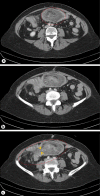

Intussusception occurs when a proximal segment of the gastrointestinal tract, called intussusceptum, telescopes into the lumen of an adjacent segment, also known as intussuscipiens. Although common in early childhood, intussusceptions are very rare in the adult population. Most intussusceptions in adults are due to a lead point, which is an identifiable pathological abnormality, in opposition to children which there are no identifiable pathological lead points. In contrast to childhood intussusception, in adults it is associated with malignant lesions, particularly in the large bowel rather than in the small bowel. Its preoperative diagnosis and treatment in adults is difficult because of nonspecific abdominal symptom and because it rarely presents with the classic triad of vomiting, abdominal pain and passage of blood per rectum. We present a 63-year-old female with an adenocarcinoma tumor being the lead point in a colocolic intussusception, who was diagnosed preoperatively with computed tomography and had a colonoscopy to rule out obstruction. She underwent right hemicolectomy with side-to-side ileocolic anastomosis and did well postoperatively. In addition, we also review the literature and discuss the value of radiological modalities, location and surgical management to try to improve the preoperative diagnosis. Computed tomography scanning with intravenous contrast is maybe the most accurate modality for diagnosis of intussusceptions in adults, and treatment is usually surgical resection without reduction, since most of the colonic lesions are malignant.